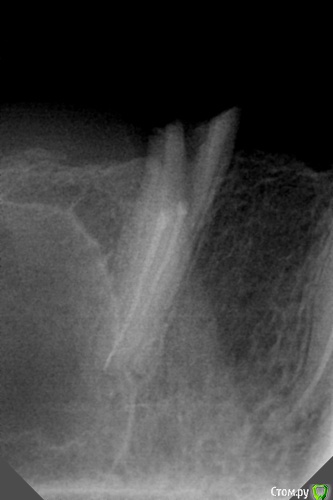

dr.Dre Опубликовано 13 июля, 2016 Поделиться Опубликовано 13 июля, 2016 Добрый день коллеги разрабатывал зуб под вкладку ,сильно закровило перфорнул. Готовилось все под мк.Как поступить удалять или пробовать пломбировать МТА? Ссылка на комментарий

art700 Опубликовано 13 июля, 2016 Поделиться Опубликовано 13 июля, 2016 Перфонули потому что канал не разработали, запломбирован тоже не ахти. Я за удаление. Ссылка на комментарий

DoctorT Опубликовано 15 июля, 2016 Поделиться Опубликовано 15 июля, 2016 Данный зуб еще до обработки под вкв был обречен без должного эндо. Ссылка на комментарий